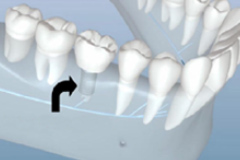

3D數碼隐形正牙

美觀時尚 · 外觀透明隐形

效果預知 · 可(kě)見正牙效果

方便省時 · 可(kě)自行摘戴

早期矯正

兒童優選 · 專為(wèi)3~12歲兒童設計

量身定制 · 針對孩子不同情況定制矯正計劃

正牙助萌 · 同步完成獲得理(lǐ)想面型